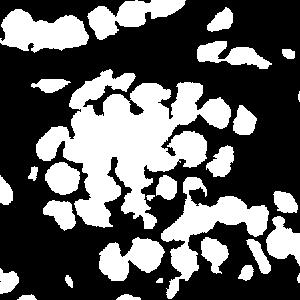

5.4 Segmentation results using detected points

The settings, including parameters in the loss function and training details, are the same as those using ground-truth points. The only difference is that compared to the ground-truth points there are errors in the detected points, i.e., false positives, false negatives and localization errors. As a result, the errors in the generated Voronoi labels and cluster labels using detected points increase, which will degrade the performance.

(a) image

(b) true mask

(c) 5%

(d) 10%

(e) 25%

(f) 50%

(g) gt points

We report the results using detected points from different ratios of initial points annotation in Table 3. Even with only 5% annotated points, the proposed framework can achieve satisfactory segmentation performance compared to the fully-supervised ones. As the annotated points increase from 5% to 50%, the overall segmentation performance becomes better. This is quite reasonable because the performance is affected by the detection results and the detection error decreases for higher annotated points ratio, as shown in Table 2.